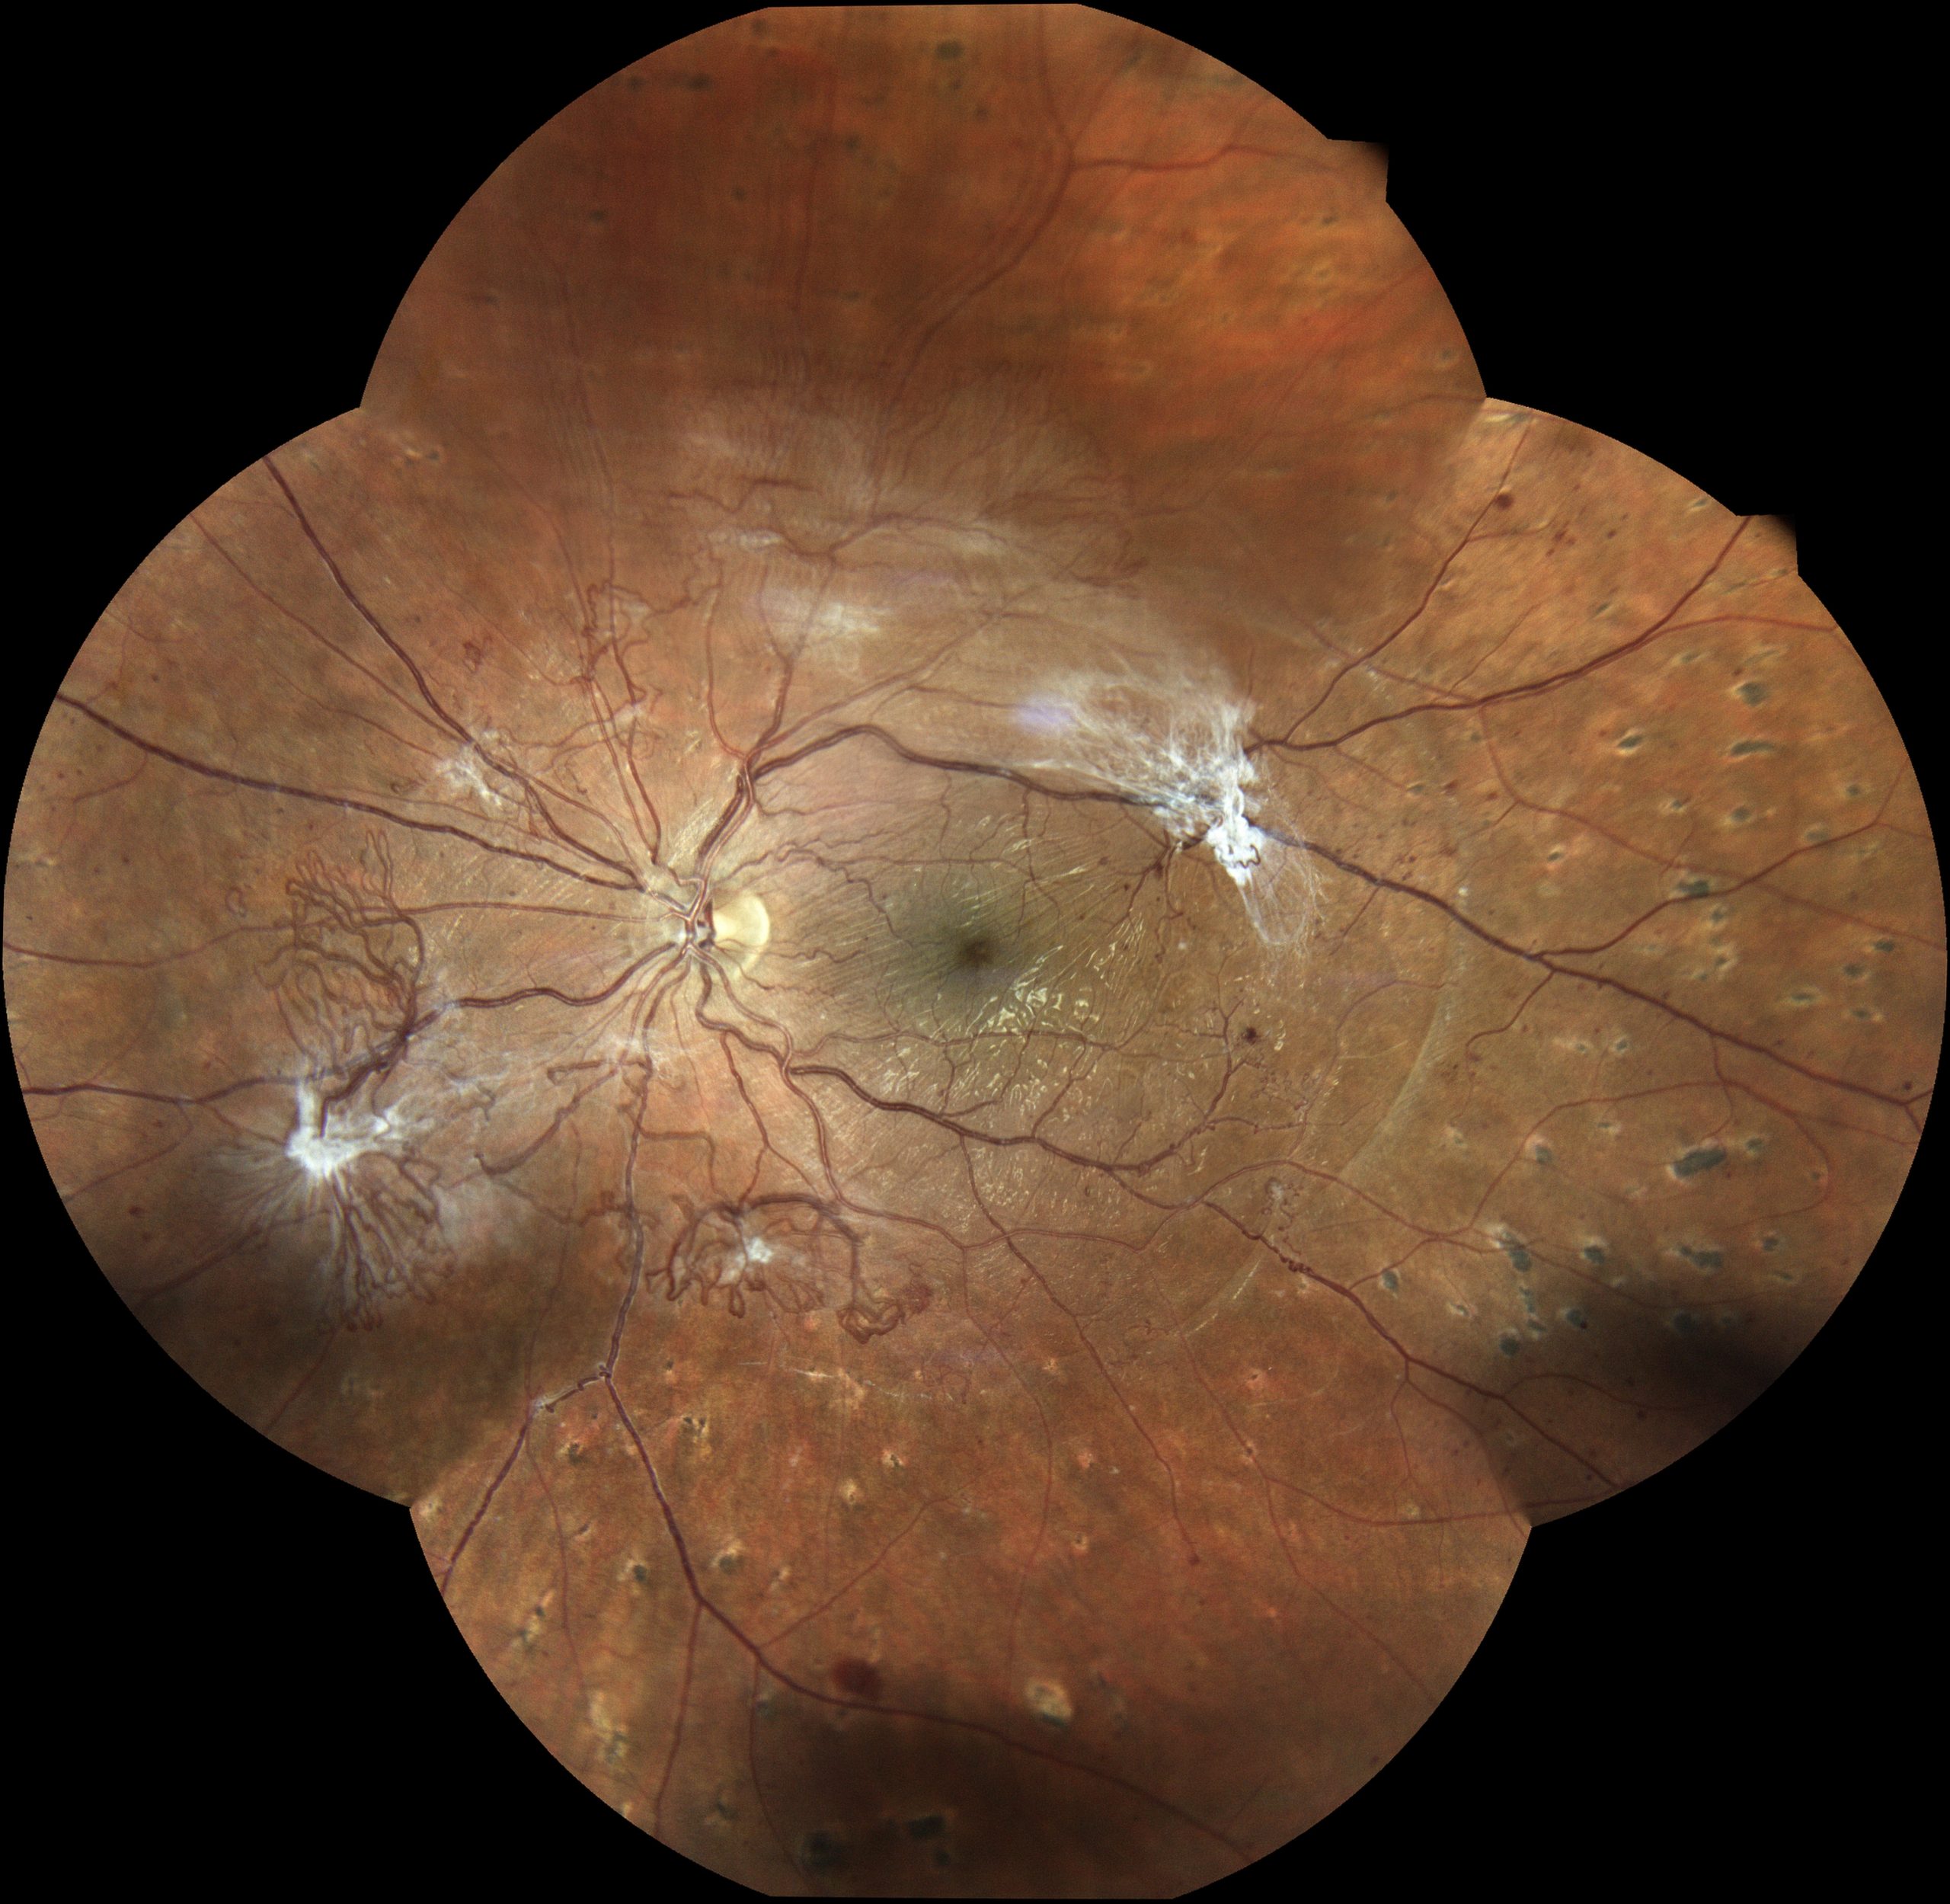

Abbildung 3: Dies ist ein Foto der Netzhaut eines Patienten mit proliferativer Diabetischer Retinopathie. In der Mitte des Bildes ist die Stelle des schärfsten Sehens zu sehen (Makula), links davon der Sehnervenkopf (Papille), noch weiter links, zur Nase hin, finden sich Gefäßneubildungen (Neovaskularisationen).

Abbildung 4: Sechs Monate später haben die Neovaskularisationen massiv zugenommen, ebenso vitreomakuläre Traktionen. Das heißt, aufgrund von Veränderungen im Glaskörper des Auges wird Zug auf die Netzhaut ausgeübt. Die Gefahr einer Netzhautablösung nimmt zu.